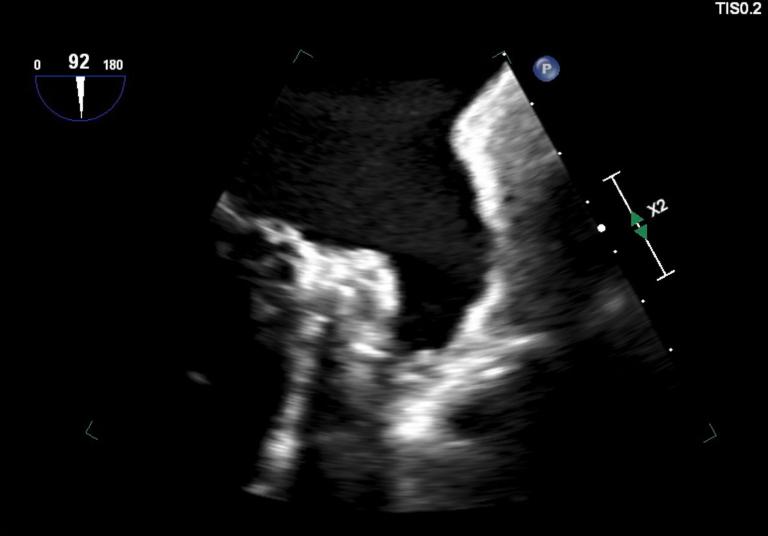

• Foreign substances can interfere with the TEE probe, causing poor image quality. • Operators should be aware of the reasons for diffusely anechoic TEE images. • Poor identification of echocardiographic artifacts may lead to adverse outcomes.

• 外来物质会干扰经食管超声心动图(TEE)探头,导致图像质量不佳。• 操作人员应了解TEE图像呈弥漫性无回声的原因。• 对超声心动图伪像识别不佳可能导致不良后果。